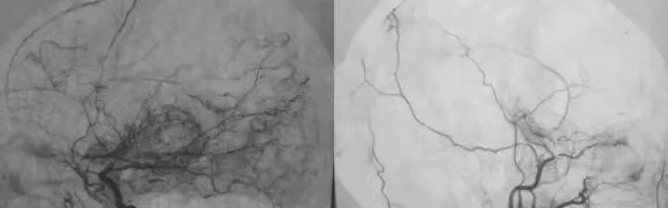

烟雾病血管造影影像

烟雾病的准确诊断及评估对于患者的治疗和预后至关重要。随着医学影像技术的进步和对疾病更深入的理解,烟雾病和烟雾病综合征的评估方案及诊断标准均取得了新的进展和共识。诊断烟雾病的“金标准”:数字减影血管造影(DSA),DSA必要的影像表现包括:以颅内颈内动脉末端部分为中心的动脉狭窄或闭塞。以及动脉期闭塞性或狭窄病变附近的烟雾病血管(异常血管网络)。